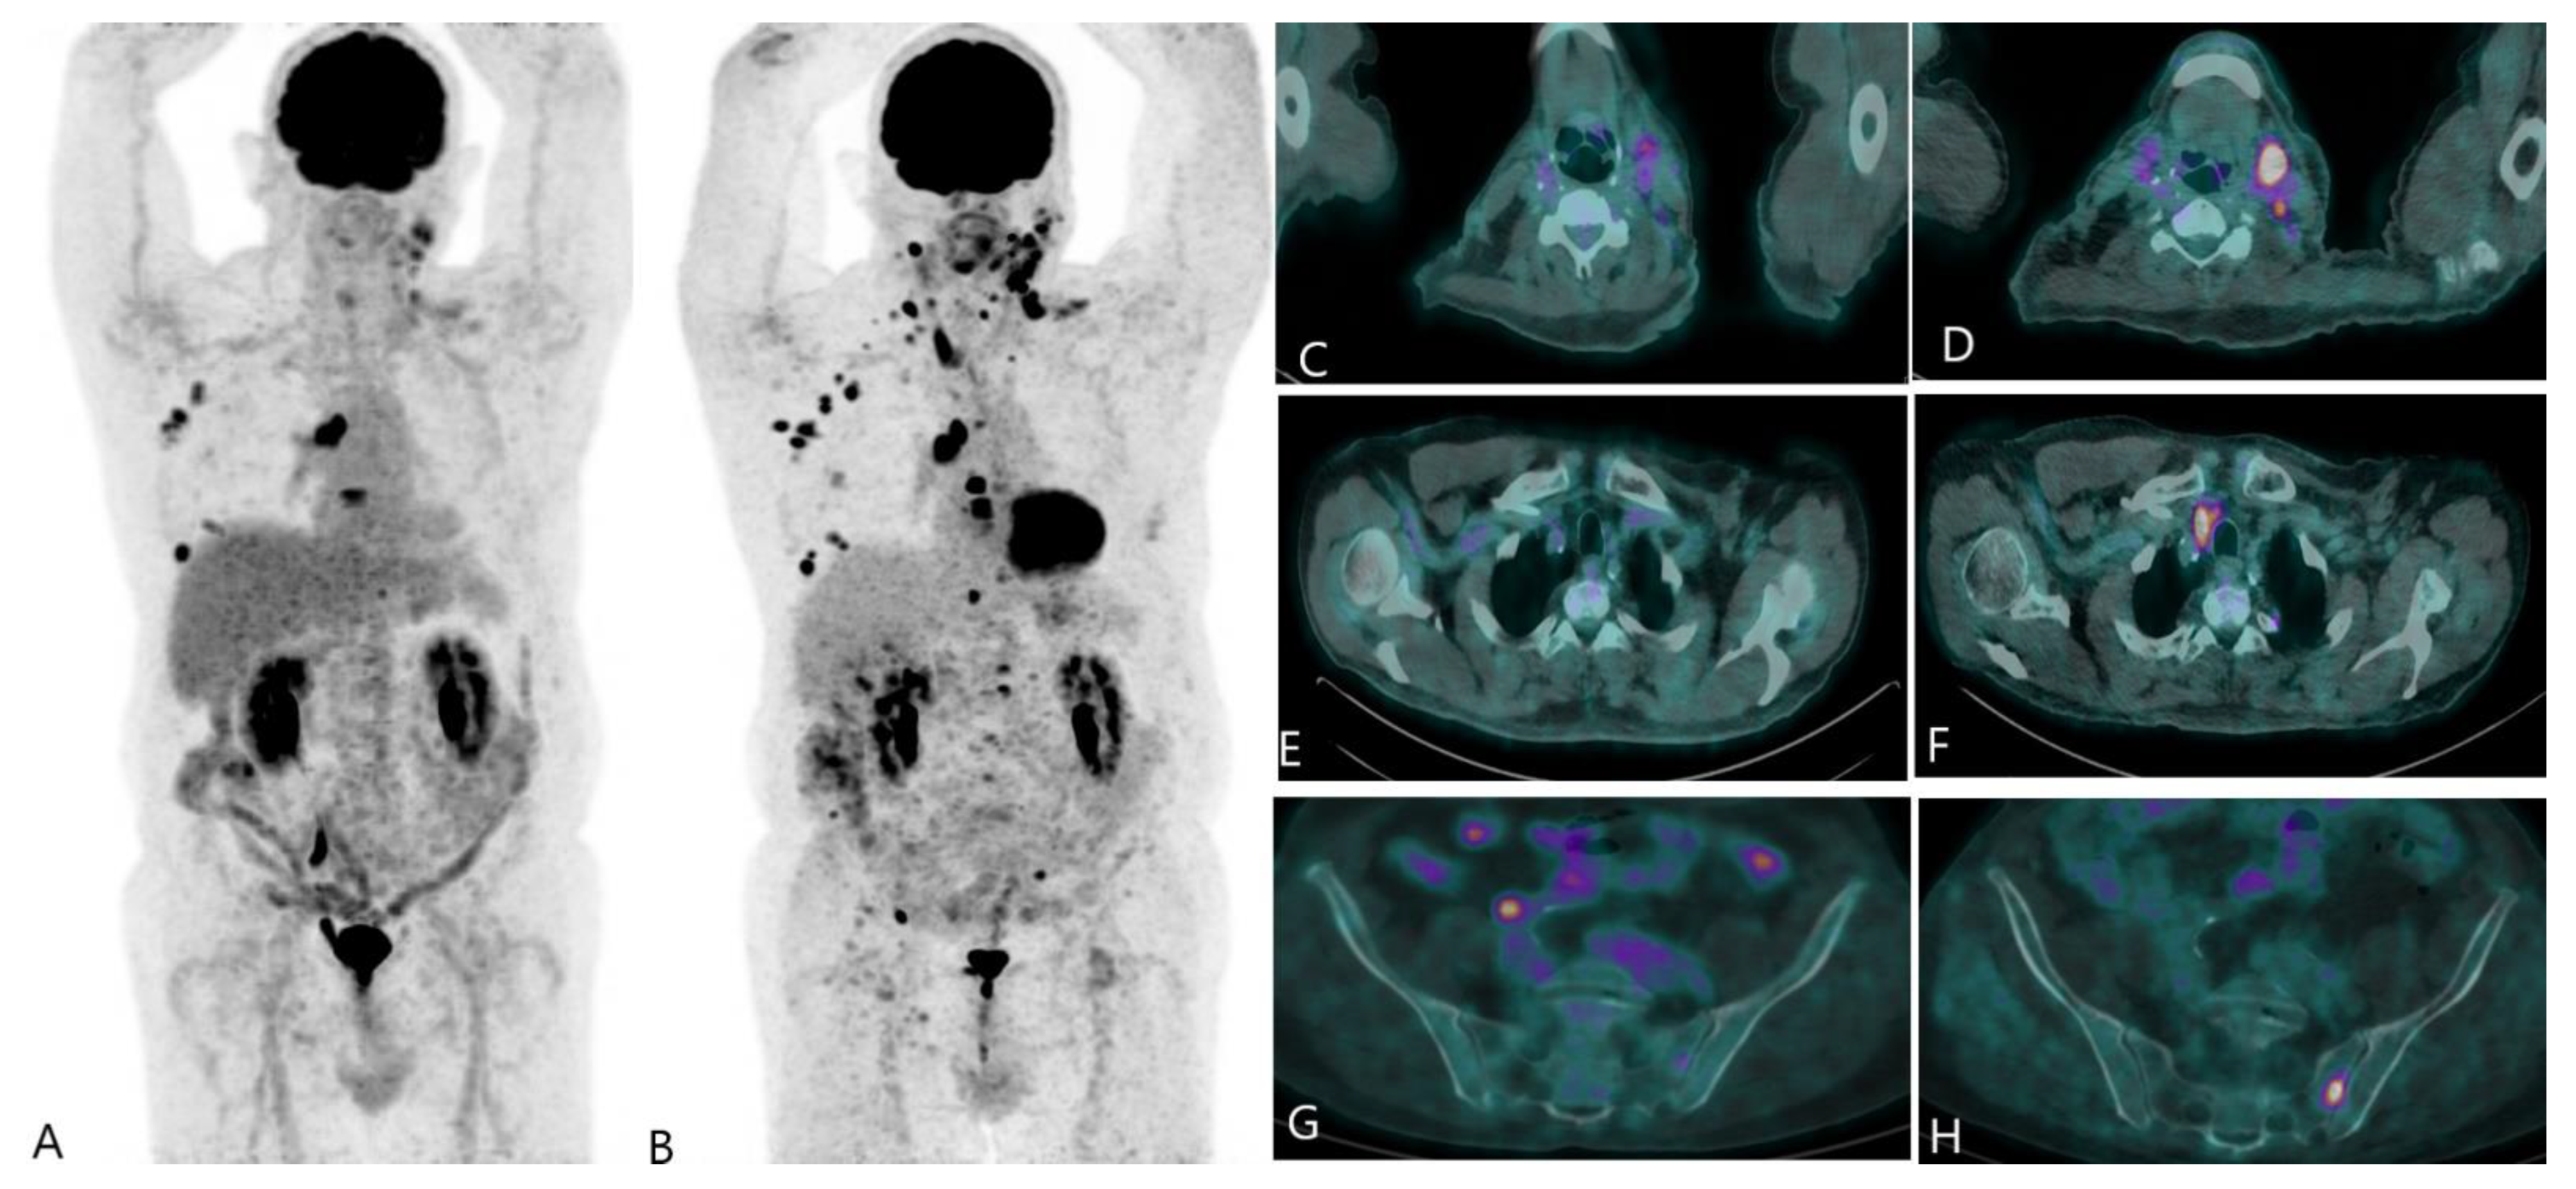

2.2. Recurrent Disease

- Hildebrandt, M.G.; Gerke, O.; Baun, C.; Falch, K.; Hansen, J.A.; Petersen, Z.A.F.; Larsen, L.B.; Duvnjak, S.; Buskevica, I.; Bektas, S.; et al. [18F]Fluorodeoxyglucose (FDG)-Positron Emission Tomography (PET)/Computed Tomography (CT) in Suspected Recurrent Breast Cancer: A Prospective Comparative Study of Dual-Time-Point FDG-PET/CT, Contrast-Enhanced CT, and Bone Scintigraphy. J. Clin. Oncol. 2016, 34, 1889–1897. [Google Scholar] [CrossRef] [PubMed]